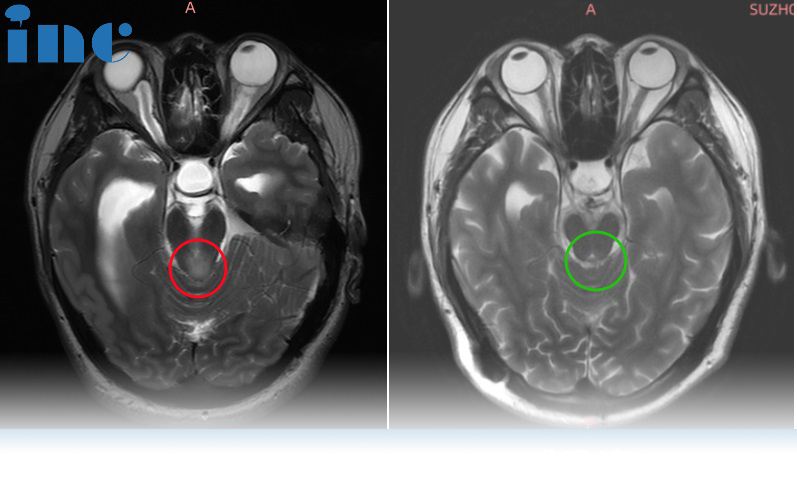

图片术前MRI影像

图片术后MRI影像